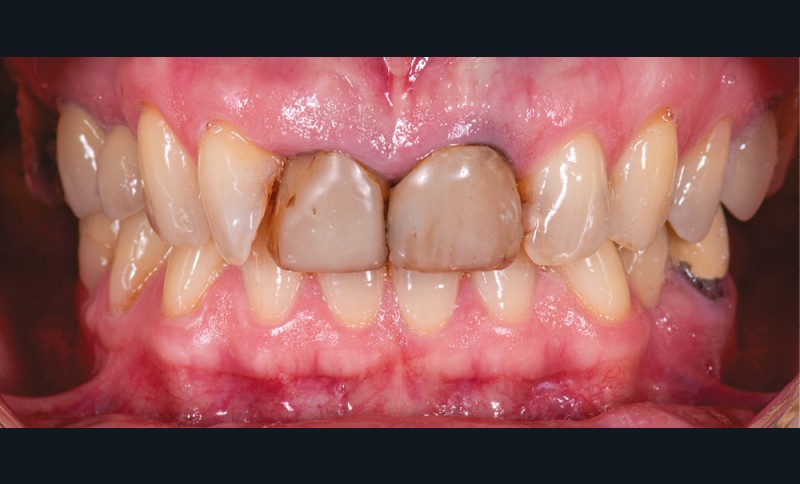

Présentation du cas (fig. 1 et 2)

Une patiente de 55 ans se présente pour une prise en charge esthétique de son sourire. Sa demande regroupe à la fois la teinte, l’encombrement incisivo-canin et l’asymétrie des incisives centrales.

Les deux incisives centrales ont été traitées endodontiquement plusieurs années auparavant et restaurées par des composites directs.

Le contrôle de plaque est insuffisant et nous notons une perte d’attache entre 12 et 11.

La patiente refuse d’emblée tout traitement orthodontique, même par aligneurs.